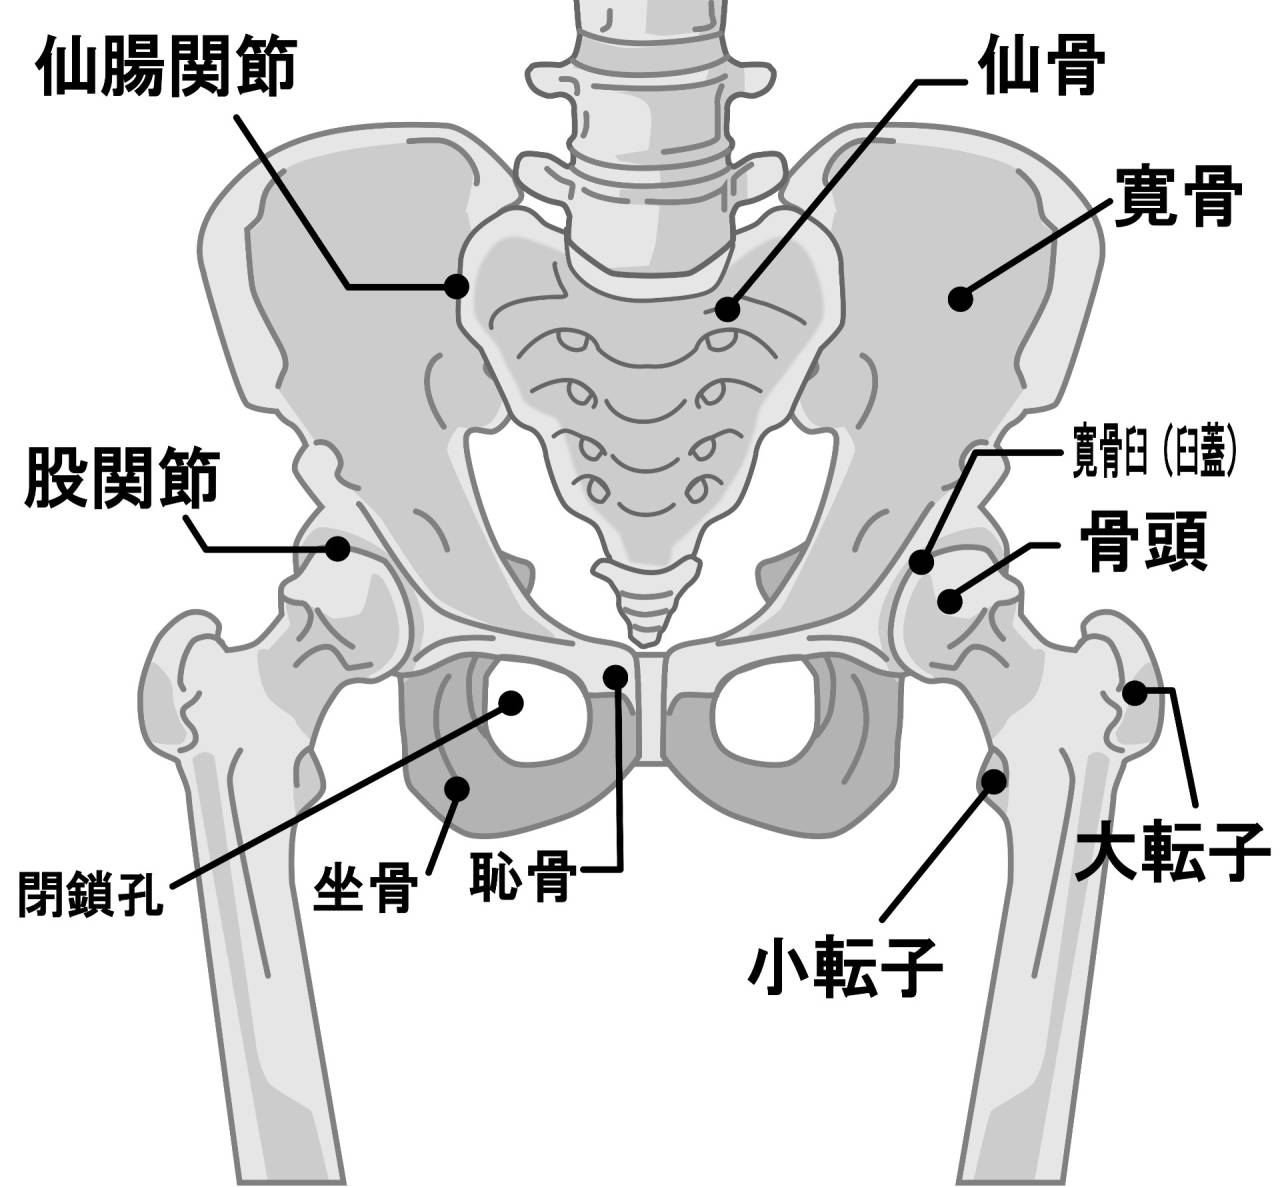

- 骨盤

- 坐骨神経痛

- 脊髄

- すべり症